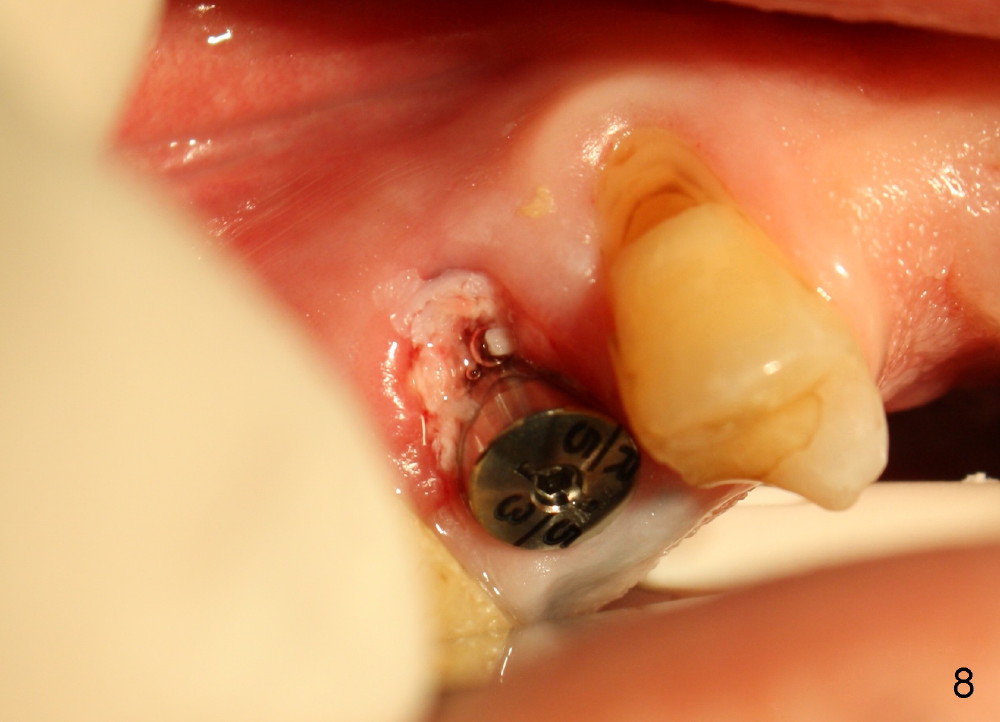

A 51-year-old man has several missing teeth in the maxilla restored by a partial denture. The tooth #4 fractures (Fig.1) and is planned to be restored by an implant (Fig.2 design: 4.5x14 mm). Immediately post extraction, osteotomy is initiated by a 2.0 mm pilot drill at the depth of 14 mm (3 mm into new bone, Fig.3). Finally a 4.5x14 mm SM (submerged) implant is placed with insertion of a 5.2x5(3) mm healing abutment (Fig.4). Mixture of autogenous bone and demineralized cortical allograft is placed in the gap between the buccal plate and the implant/abutment (Fig.6), covered by collagen membrane (Fig.7 M; P: partial denture). In fact the membrane is fixed between the implant and the healing abutment lingually. The wound is finally covered by perio dressing (Fig.5 ^). The patient returns 5 days postop. The perio dressing is removed unintentionally. It appears that the membrane has started to be resorbed (Fig.8).